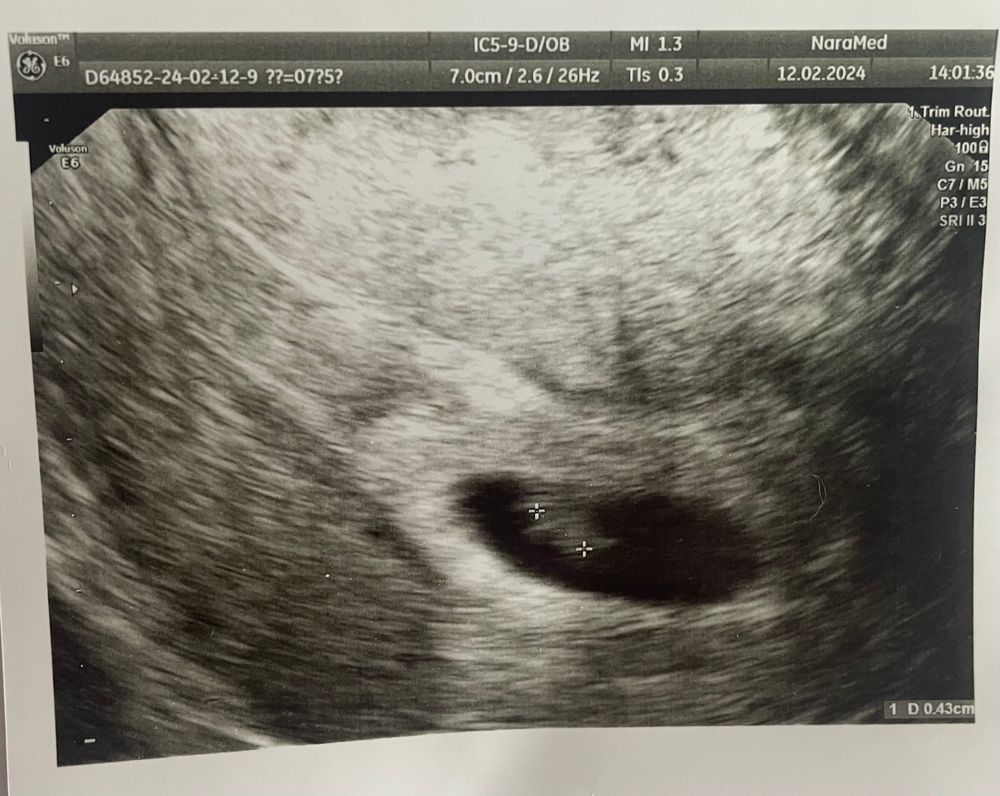

Марина, ну вот 5 числа 3 мм был, а вчера она как-то померила 0.43 см… я и удивилась… но смотрела супер быстро, супер бегло… хотя блин платная клиника… не знаю что делать…

Елена, это вчерашнее УЗИ… ну и заключение выглядит как-то странно… размер ПЯ - это не диаметр, это, судя по всему, в 1 измерении… нет ни размера ЖМ, ни КТР… ничего…

Анастасия , вижу пя 22 мм, ктр 4 мм. С 3 мм до 4 за неделю это плохой рост. Жм визуализируется, не все его замеряют.